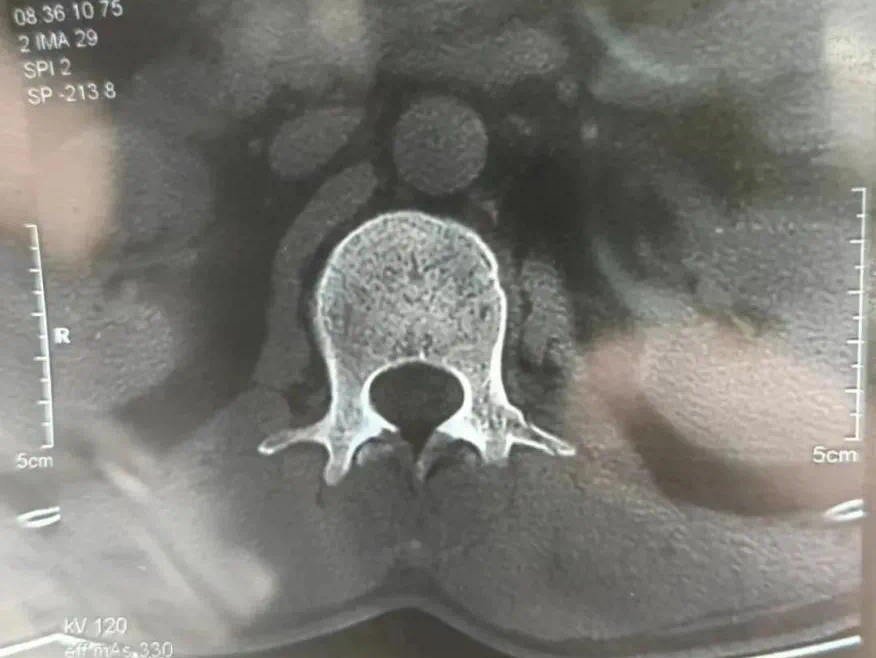

发电站路段修通,部分通讯恢复正常,王磊的精神稍稍放松了一些,这时他感到腰部剧烈疼痛,在领导和同事们的劝说下,王磊终于去医院就诊,被诊断为“腰椎横突骨折”,差一点就伤到肾脏。